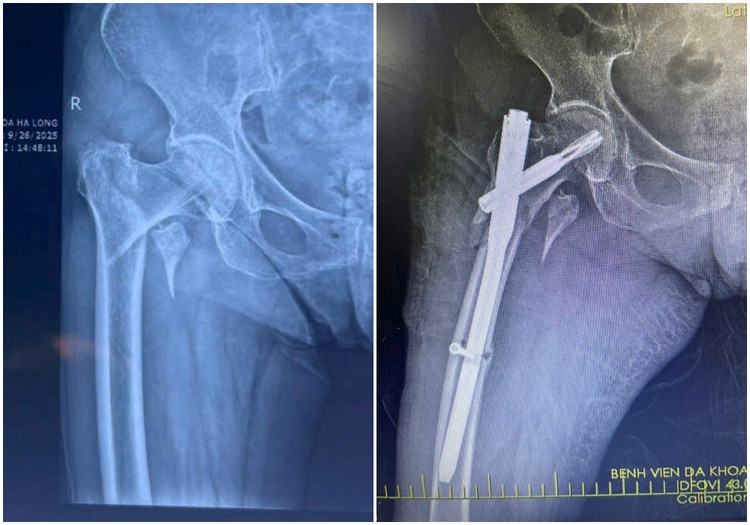

xuong-dui-2.jpg

Hình ảnh X-quang gãy liên mấu chuyển xương đùi trái của bệnh nhân H (88 tuổi) được kíp mổ phẫu thuật kết hợp xương ít xâm lấn - Ảnh BVCC